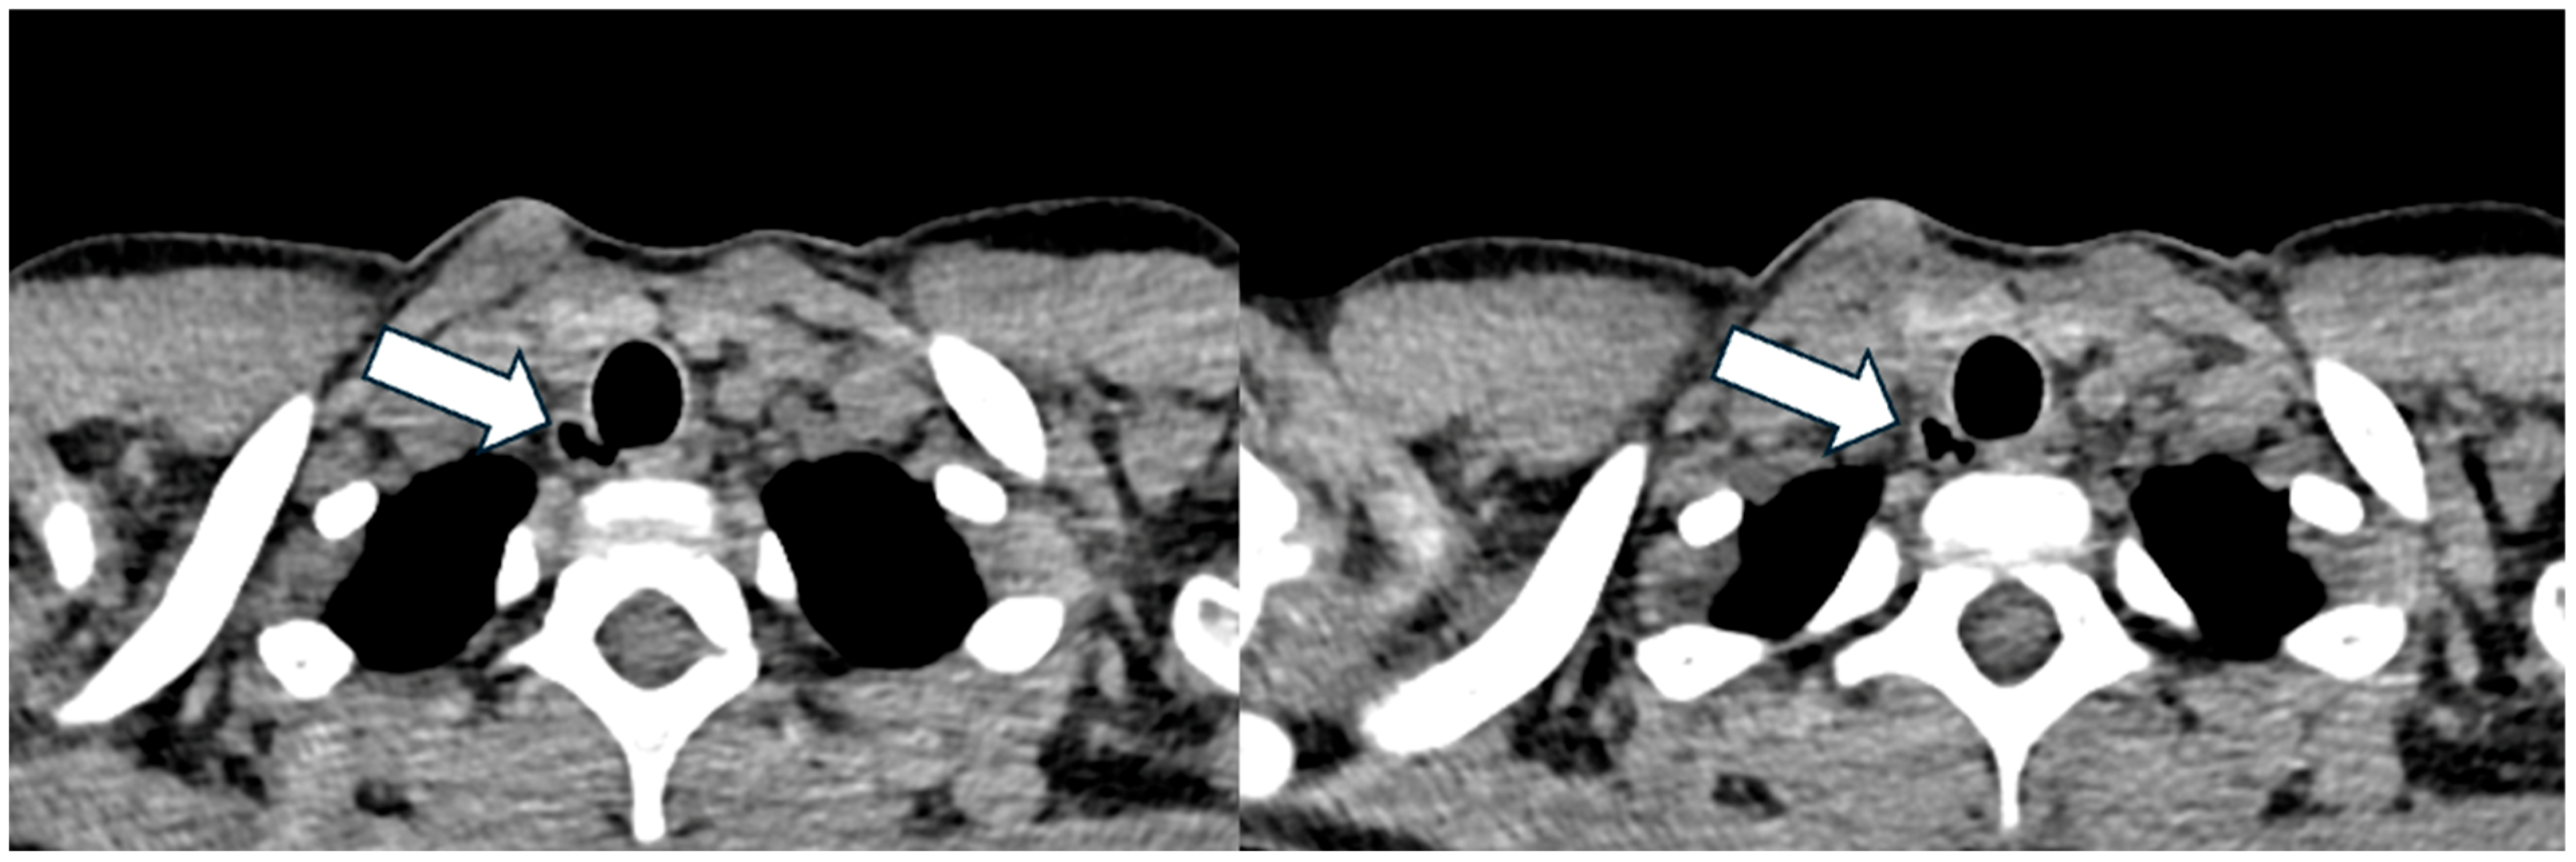

3.1. Patient 1

| 30, M | F508del/ E585X | SA, PA | 73 | 36 | 2, 10 mm, right posterolateral at T2 level | Yes | Visible radiologically and endoscopically | Bronchoscopy after 6 months: stable TD; occurrence of punctiform paracarenal TD |